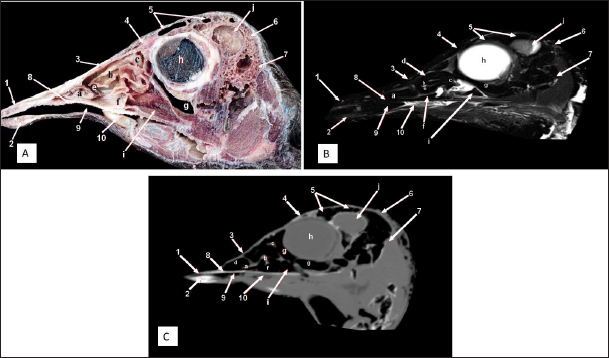

Fig. 3. Sagittal cross section of the adult ostrich head—level 2. A) Photograph of a paramedian sagittal anatomical section (medial view). B) MRI and C) computed tomography images showing: 1- Os premaxillare, 2- Os dentale, 3- Os nasale, 4- Processus. frontalis, 5- Frontal sinus, 6- Os parietale, 7- Os temporalis, 8-Palate, 9- Oral cavity, 10- Tongue, a- Rostral nasal concha, b- Middle nasal concha, c- Caudal nasal concha, d- Dorsal nasal meatus, e- Middle nasal meatus, f- Ventral nasal meatus, g- Infraorbital sinus, h- Orbit containing eye ball, i- Choanal opening and j-Cranial cavity.

Fig. 4. Sagittal cross section of the adult ostrich head—level 3. A) Photograph of a paramedian sagittal anatomical section (medial view). B) MRI and C) computed tomography images showing: 1- Os premaxillare, 2- Os nasale, 3- Frontal sinus, 4- Processus.frontalis, 5- Cerebral hemisphere, 6- Os frontalis, 7- Os dentale, 8- Oral cavity, 9- Tongue, a- Middle nasal concha (rostral part), b- Middle nasal concha (caudal part), c- Ventral nasal meatus and d- Vomer.

Fig. 5. Sagittal cross section of the adult ostrich head—level 4. A) Photograph of paramedian sagittal anatomical section (medial view). B) MRI and C) computed tomography images showing: a- Rostral nasal concha, b- Middle nasal concha, c- Caudal nasal concha, d- Middle nasal meatus, e- Ventral nasal meatus, f- Infraorbital sinus, g- Orbit containing eye ball, h- Frontal sinus and i- Os temporalis.

The nasal conchae exhibited in the MRI images as bright (high or hyperintense signal intensity) to gray (low or hypointense signal intensity) structures that could be divided into three parts: rostral, middle, and caudal conchae, which correlated to the morphological examinations. In contrast, the nasal conchae could not be recognized clearly on CT images compared to those obtained after MRI (Figs. 25 B and C). The paranasal sinuses with other structures could be identified using both CT and MRI. The nasal septum and paranasal sinuses revealed a white bone border (high signal intensity), soft tissue was grey (low-to-intermediate signal intensity), and they contained black gas, so both the CT and MRI scans showed little signal intensity (Figs. 15B and C and 79B, C, E, F).